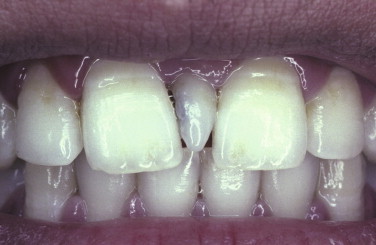

Hutchinson’s incisors are manifestations of what congenital disease?

Congenital syphilis